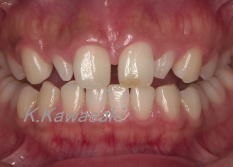

| 「前歯で物をかむことが出来ない、何とかしてほしい」と来院されました。奥歯にも虫歯が多くありました。また横顔は少し受け口でした。精密検査の結果、矯正治療後全体的に治療する事になりました。 |

| 抜歯矯正によりかみ合わせを整え、セラミックの歯を装着しました。見た目、機能の改善が出来ました。口元も美しくなりました。 |